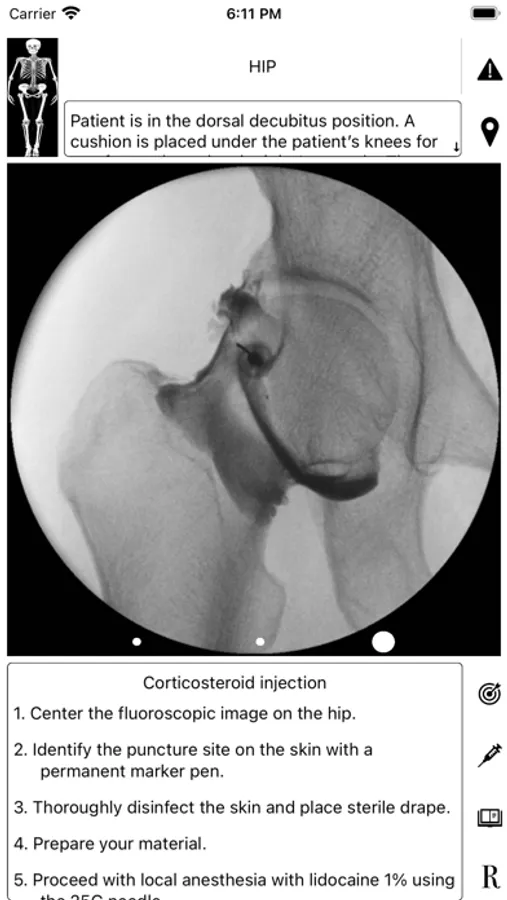

ArthroGuide targets residents, fellows, and physicians who perform fluoroscopically guided arthrograms and pain management injections, including spinal injections. It results from more than 25 years of experience in performing and teaching these procedures.

A visual interface facilitates a quick and efficient review of the information. Find information on patient positioning, puncture site, equipment used, products injected, and the steps to perform therapeutic injections and arthrograms preliminary to an MRI or CT scan. Access relevant references online using hyperlinks directly from within the application. Take advantage of procedural tips, recommendations, and cautionary statements.

ArthroGuide Screenshots